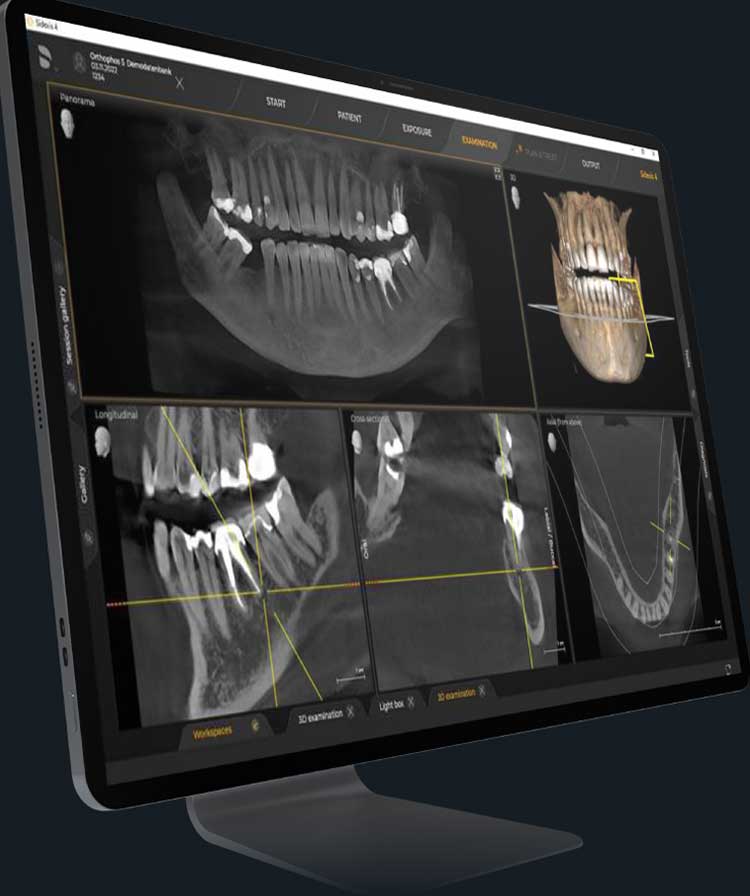

3D Imaging with CBCT Technology

3D Imaging with CBCT Technology

Our clinic features CBCT (Cone Beam Computed Tomography) 3D X-ray technology, which offers comprehensive 3D images of your teeth, bones, and surrounding structures.

This detailed imaging allows for accurate diagnosis of complex dental conditions such as impacted teeth, root fractures, and bone structure abnormalities. It also aids in precise treatment planning for procedures like dental implants, orthodontics, and endodontics, reducing the risk of complications and improving overall treatment outcomes.

CBCT-Enhanced Invisalign ClinCheck Planning

By integrating CBCT data with Invisalign’s ClinCheck software, we can plan your tooth alignments with greater accuracy.

This combination provides a detailed view of your bone and tissue structure, enhancing the predictability of your treatment and ensuring a perfect fit for your aligners. The comprehensive imaging allows us to create a highly customised Invisalign treatment plan that meets your unique needs, resulting in better, more predictable outcomes.